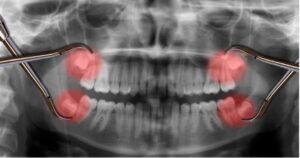

1. Thế nào là răng mọc ngầm Răng mọc ngầm là những răng mọc nhưng